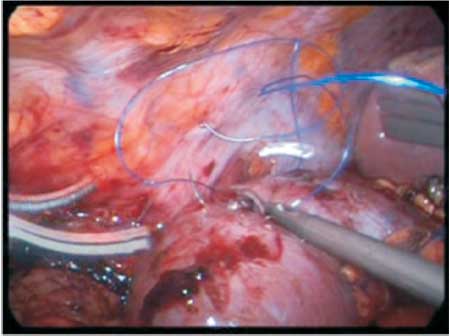

The patient was placed in the left half-lateral decubitus position with pads to relieve the pressure over some areas. Two 10mm trocars and two 5mm trocars were used, one at the umbilicus where it was inserted a 30o optical the other 10mm was inserted 12 cm from this one in the middle line. One 5 mm trocar was inserted at the midline between the right anterosuperior iliac spine and the umbilicus and at last a 5 mm trocar is inserted two fingers below the furcula to move the liver. The right colon and duodenum were repelled to the midline and the kidney with its perirenal fat was identified. The fat was removed from the lateral part (Figure 3) until the capsule could be seen, remaining just slightly close to the hilum. At this moment, the patient was placed in Tredlemburg position in order to be investigated the correct position of the kidney that was going to be fixed. Three 2.0 polypropylene threads were inserted into the lateral border of the kidney and they were temporarily fixed into the lateral abdominal wall. Another suture of the same thread was passed through the upper pole of the kidney and afterwards into the infrahepatic peritoneum which was tied up to the portion that was more proximal to needle with a second polymer clip (Figure 4). Afterwards the remained threads that were inside the cavity were passed longitudinally through the psoas muscle (Figure 5) avoiding the genitofemoral nerve, and they were tied as the previous one. The fixation was tested with the operative table placed in anti-Trendlemburg position, the hemostasis was checked and a laminar drain was left in the abdominal cavity.

Figure 4 - Insertion of the threads through the convex border of the kidney and its fixation to the lateral of the abdominal wall.